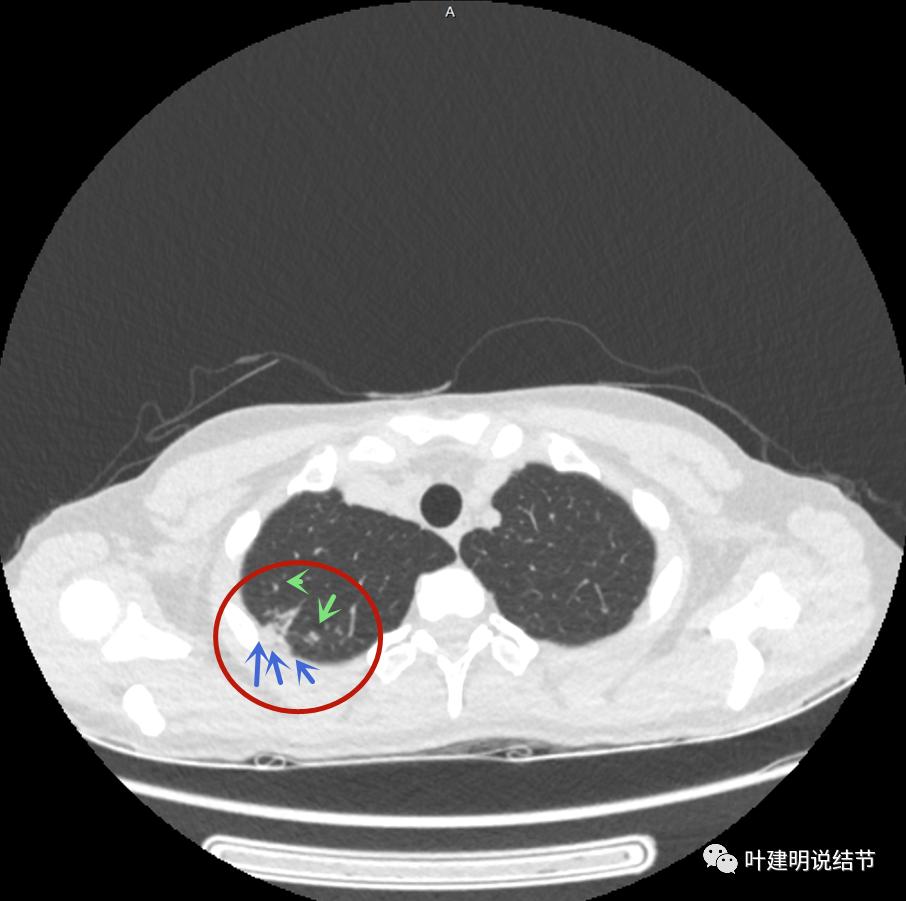

病灶邻近胸膜异常增厚(蓝色箭头)

有卫星灶(绿色箭头),邻近胸膜明显增厚,且模糊,边不清

邻近胸膜增厚